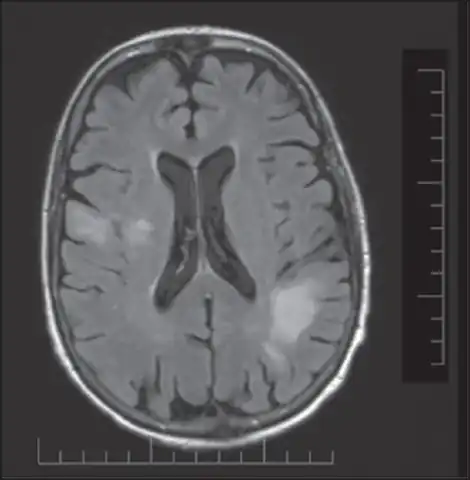

| T2-weighted MRI showing progressive multifocal leukoencephalopathy | |

PML is diagnosed in a patient with a progressive course of the disease, finding JC virus DNA in spinal fluid together with consistent white-matter lesions on brain magnetic resonance imaging (MRI); alternatively, a brain biopsy is diagnostic[1] when the typical histopathology of demyelination, bizarre astrocytes, and enlarged oligodendroglial nuclei are present, coupled with techniques showing the presence of JC virus.[12]

Characteristic evidence of PML on brain CT scan images are multifocal, noncontrast enhancing hypodense lesions without mass effect, but MRI is far more sensitive than CT.[12] The most common area of involvement is the cortical white matter of frontal and parieto occipital lobes, but lesions may occur anywhere in the brain, such as the basal ganglia, external capsule, and posterior cranial fossa structures such as the brain stem and cerebellum.[12] Although typically multifocal, natalizumab-associated PML is often monofocal, predominantly in the frontal lobe.[12]

High signal intensity lesion of white matter of dorsal right frontal lobe/right frontal operculum